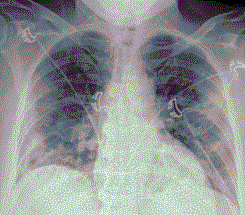

Стандартная РГ имеет низкую чувствительность в выявлении начальных изменений в первые дни заболевания и не может применяться для ранней диагностики. Информативность РГ повышается с увеличением длительности течения пневмонии. Рентгенография с использованием передвижных (палатных) аппаратов является основным методом лучевой диагностики патологии ОГК в ОРИТ. Применение передвижного (палатного) аппарата оправдано и для проведения обычных РГ исследований в рентгеновском кабинете. В стационарных условиях относительным преимуществом РГ в сравнении с КТ являются большая пропускная способность. Метод позволяет уверенно выявлять тяжелые формы пневмоний и отек легких различной природы, которые требуют госпитализации, в том числе направления в ОРИТ.

5. Рекомендовано проведение лучевого исследования пациентам при среднетяжелом, тяжелом и крайне тяжелом течении ОРИ с целью медицинской сортировки, оценки характера изменений в грудной полости и определения прогноза заболевания:

- выполнение КТ легких без внутривенного контрастирования в стационарных условиях или в амбулаторных - при показаниях к госпитализации;

- выполнение РГ легких в двух проекциях, если проведение КТ в данной медицинской организации/клинической ситуации невозможно.